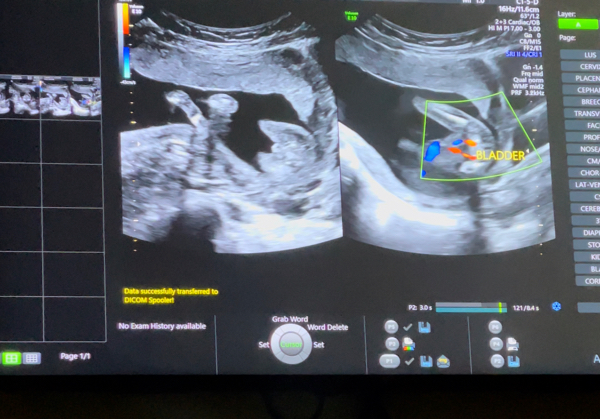

انا رحت ب الاسبوع ال ١٤ عند اخصائية اشعه وقالت لي ولد شفت شكل هرمي

وبعدها بكم يوم تعبت ورحت دكتورة نساء وولاده وقلتلها اني قبل كم يوم رحت ل اخصائية اشعه ويوم كشفت قالتلي قالتلك جنس الجنين قلتلها ايه قالت لي ولد قالت اه هو ولد بس انا خفت انه الحبل السري وبعدين قلتلها يعني هو اكيد ولد يادكتوره قالت طالما انا وهي قلنا نفس الجنس معناته صح

عاد لازم اروح اتاكد وزوجي مرررره فرح مررره يارب يارب اني اتاكد واتطمن 🥺🥺